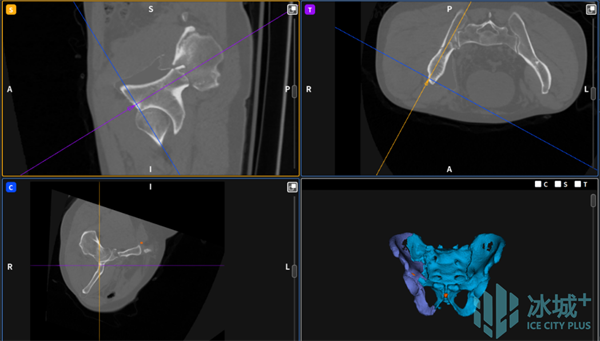

图3 人工智能复位规划

术中,刘建宇教授对复位位置及路径进行预览并确认规划后,分别将手术机械臂与患者健侧、患侧稳定固定把持,并使用电动骨科牵引架与患者下肢稳定连接,采用力-位协同控制模式进行机器人精准闭合复位,在全程多角度实时可视监控和自动规划引导下,安全完成骨盆骨折闭合复位,术中透视验证复位结果满意。最后,他操作机器人进行了螺钉通道置入规划,在实时动态三维可视化导航下,精准置入螺钉,完成了该例骨盆骨折的微创治疗。“数智化微创手术”用时2小时,患者腹部仅留有5个长度1cm的手术切口,术中出血量仅有50ml。